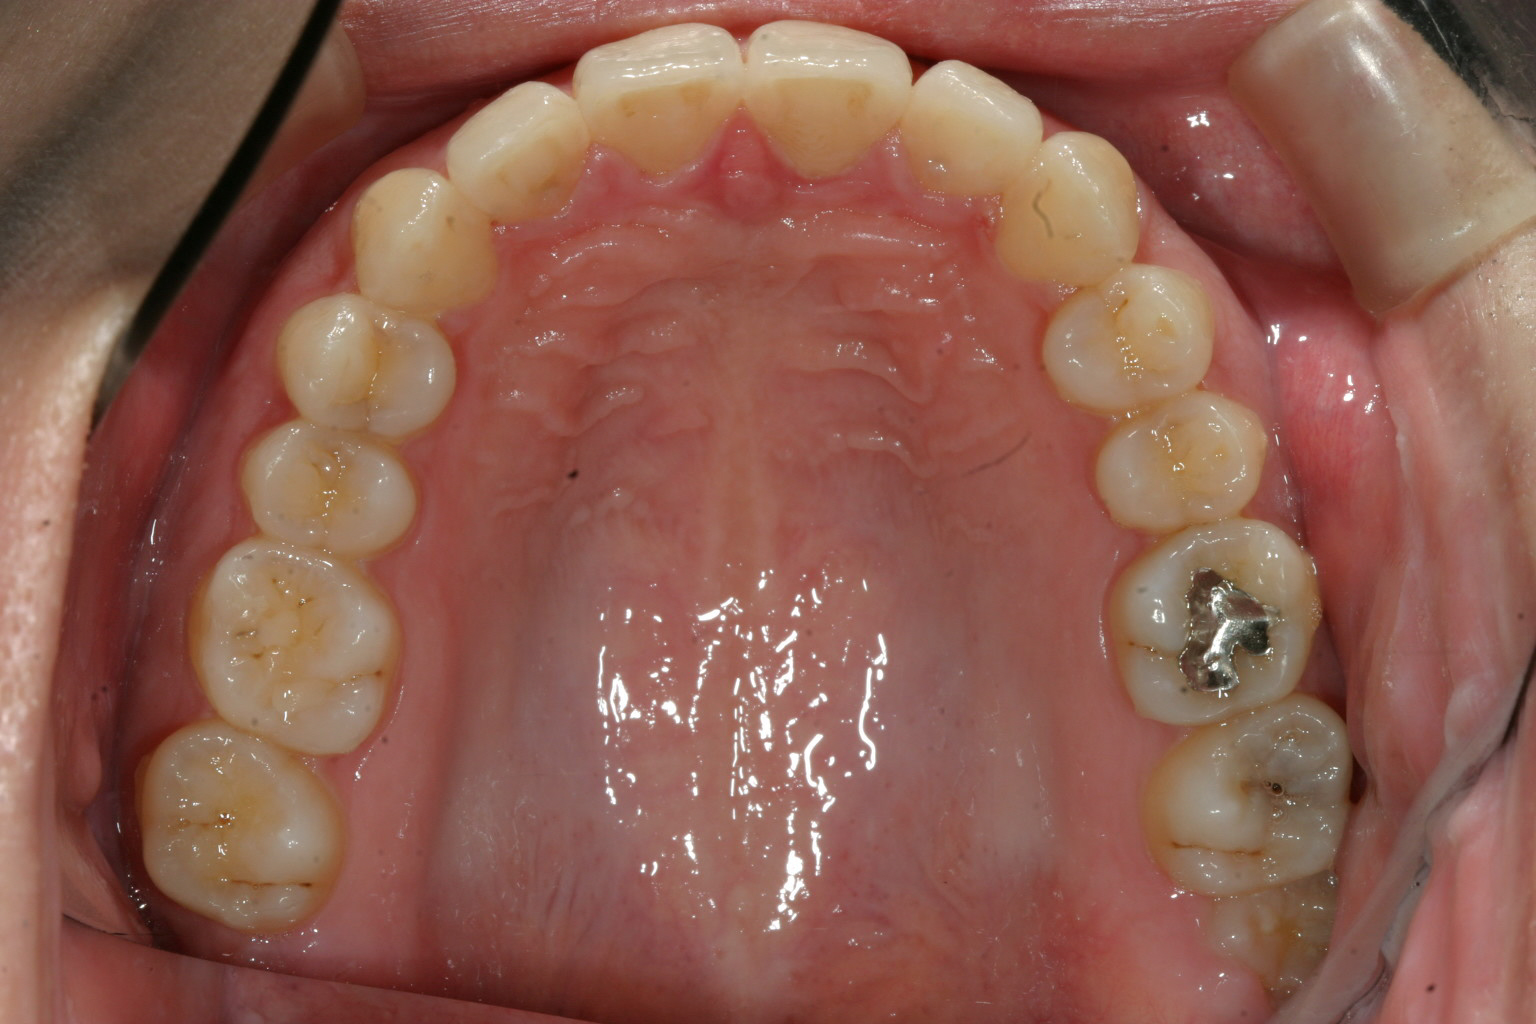

インビザラインで綺麗に治しました。

僅か1年2ヵ月で抜歯もせずここまで治りました。 如何でしょうか?